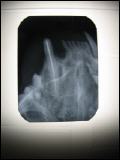

Hochauflösendes digitales dentales Röntgen

Zahnfüllung gefüllter Eckzahn nach Wurzeltherapie